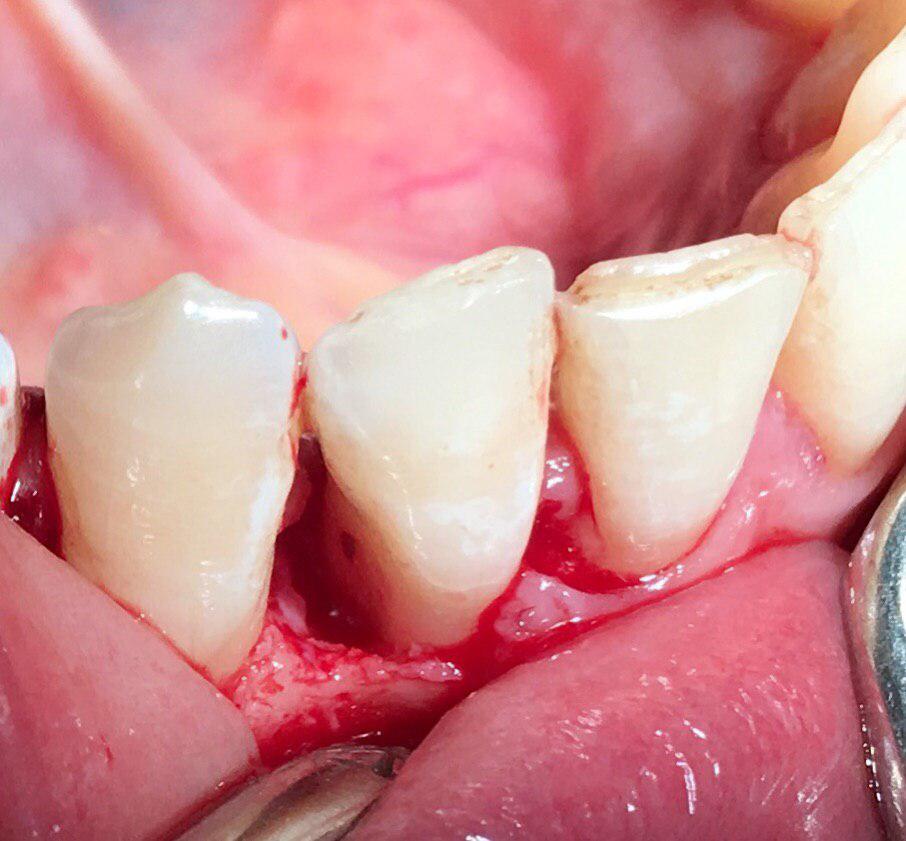

جراحی پیوند لثه جهت افزایش لثه چسبنده و پوشش ریشه و بهبود تحلیل لثه

جراحی افزايش طول تاج جهت آماده سازی دندانها برای ترمیم و گذاشتن روکش